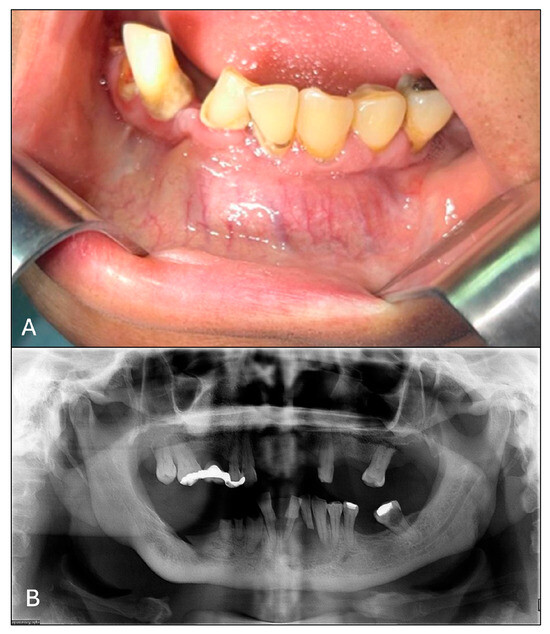

2.1. Examination